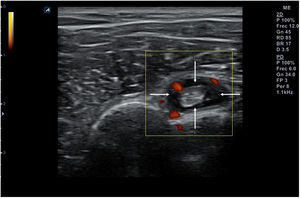

Técnica de exploraciónLa exploración ecográfica se realiza con sonda lineal de alta frecuencia (7,5-12MHz). Se debe hacer de forma estandarizada en las distintas áreas anatómicas, que permita identificar los diferentes tejidos, tanto normales como patológicos, observados en reposo y en movimiento. Los signos ecográficos patológicos habituales son la colección hipo- o anecoica comprimible y desplazable en recesos articulares en los derrames (fig. 10), el engrosamiento hipo- o anecoico del tejido en una vaina sinovial con o sin líquido en la tenosinovitis (fig. 11), la interrupción y espiculación de la línea cortical en las erosiones óseas (fig. 12), la aparición de material ecogénico en el espacio sinovial o articular en las sinovitis y el pannus respectivamente, y la presencia de señal doppler en los procesos con inflamación activa (fig. 13). Deben identificarse en 2 planos distintos para evitar la confusión por la presencia habitual de artefactos. Se ha de aplicar gel suficiente que permita el contacto de toda la superficie de la sonda con la piel, evitando el aire entre ambos, y se debe ejercer una presión firme pero no excesiva, que impida colapsar los neovasos visibles mediante el doppler. Estos serán más fáciles de encontrar con la articulación en flexoextensión fisiológica.

La ecografía permite detectar sinovitis y erosiones de forma mucho más precoz que la radiografía convencional (RX), por lo que es útil para el diagnostico y seguimiento. Su inmediatez y disponibilidad la hacen más aplicable que la RM. Además, detecta inflamación con mayor sensibilidad que la exploración física (EF) y permite distinguir entre derrame y sinovitis en escala de grises27. Con la técnica de power-doppler permite localizar neovascularización sinovial relacionada con actividad inflamatoria, siendo la sinovitis el mejor predictor de erosión radiográfica28,29.Esto la hace especialmente eficaz para el diagnóstico en fases iniciales de la artritis cuando la EF no puede aclarar aún la existencia de signos inflamatorios articulares, si bien sus hallazgos no son específicos de artritis reumatoide. También permite valorar la extensión de la artritis, mediante la exploración ampliada de las articulaciones de manos, muñecas y metatarsofalángicas, permitiendo detectar inflamación en articulaciones aún asintomáticas30,31. Hay datos sólidos que demuestran la capacidad de la ecografía para la detección más precoz de erosiones que la RX32,33, aunque su capacidad es inferior a la de la RM33–35.